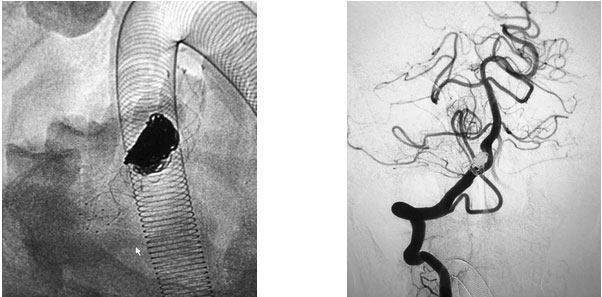

在充分准备后,张琪博士在刘春医生、周林华医生协助下为患者进行了支架辅助动脉瘤栓塞手术。填入弹簧圈后,再置入支架,完全释放后,造影显示动脉瘤无显影,支架覆盖良好,载瘤动脉通畅,撤出微导管输送系统,复查双侧椎动脉造影显示远端血流通畅。

▲ 术后,造影显示动脉瘤无显影,栓塞成功